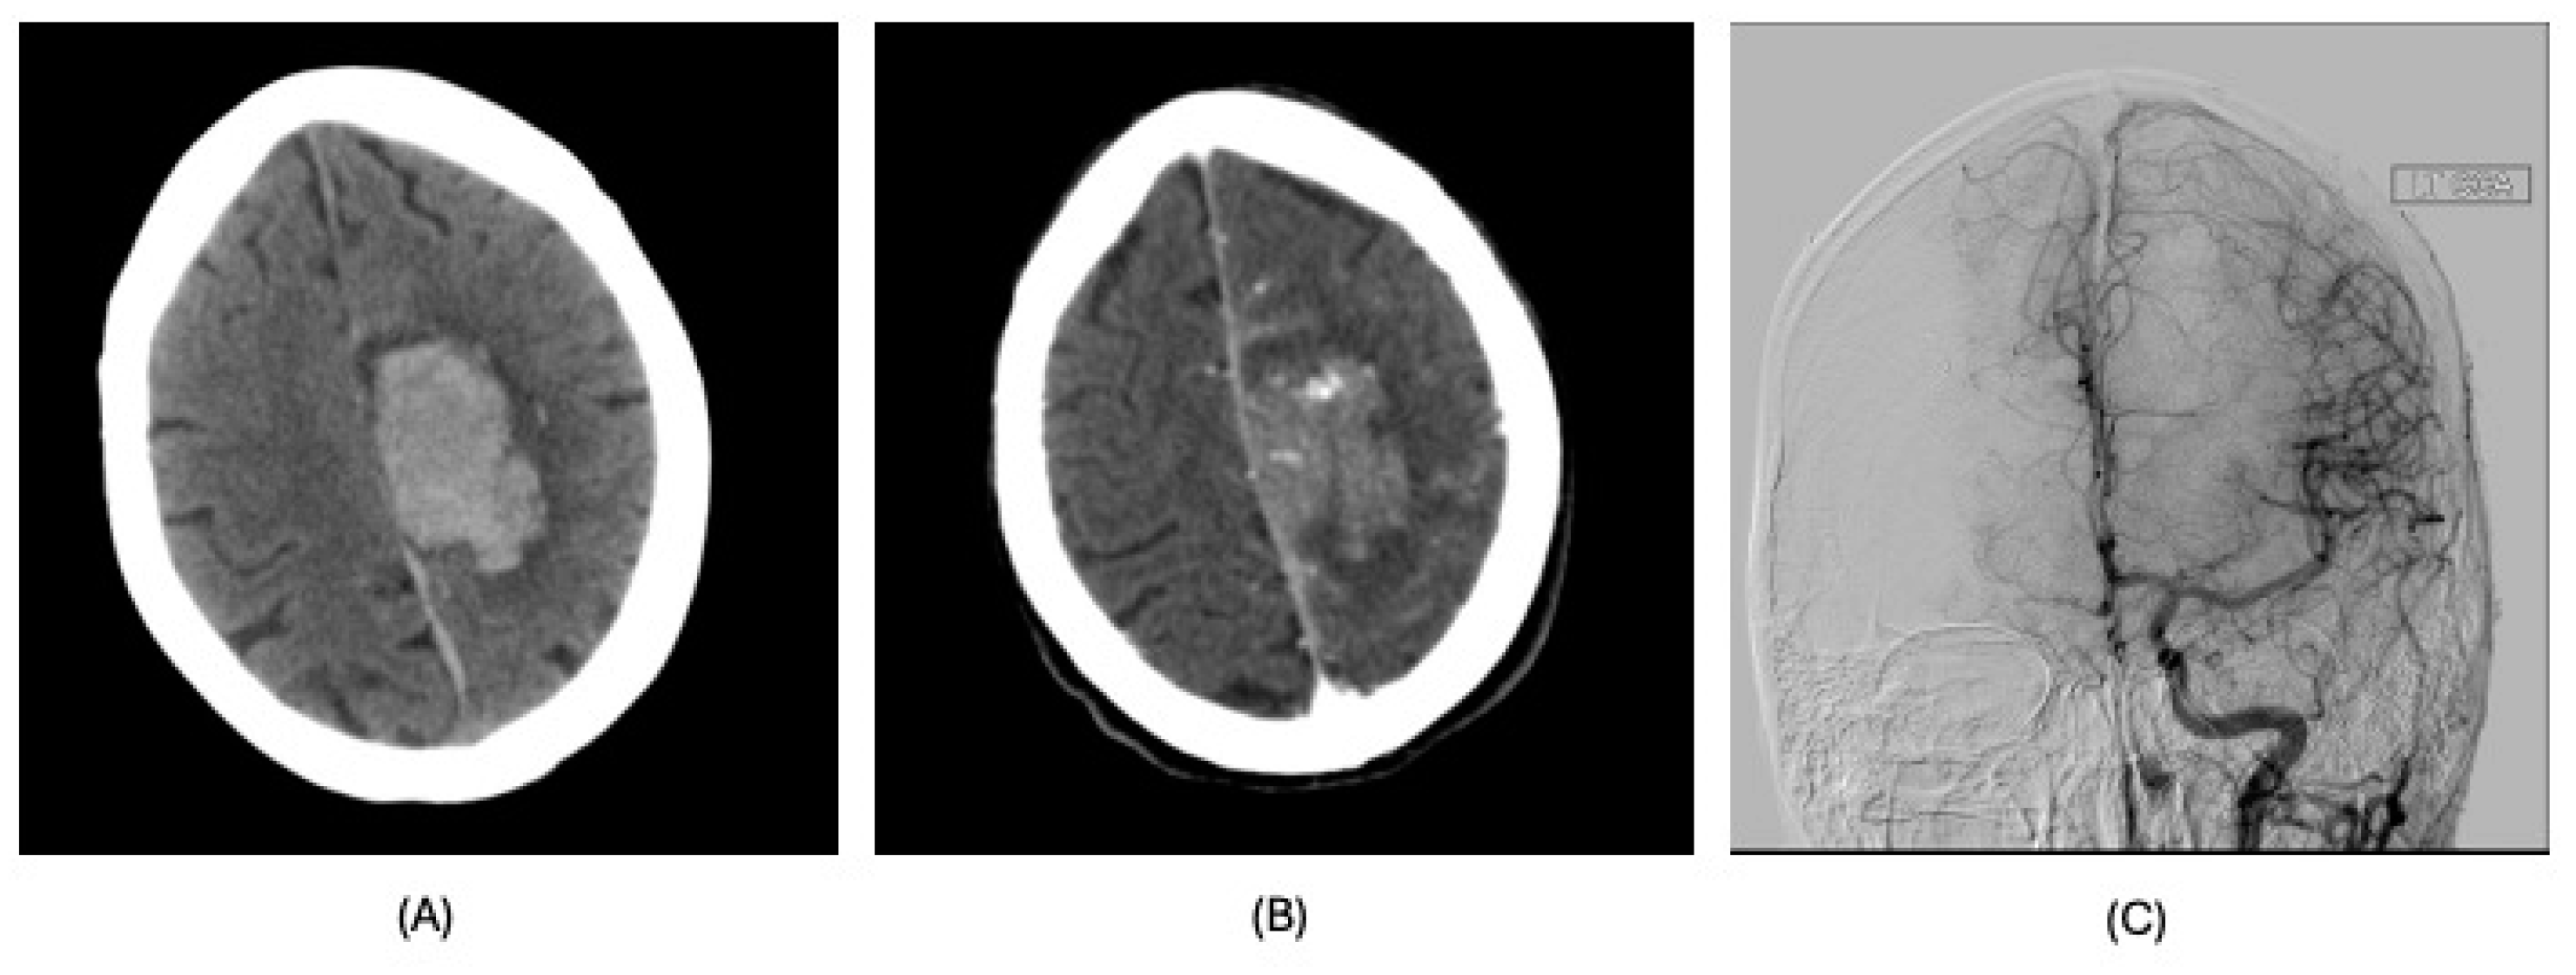

| Diagnosis | Lobar intracranial hemorrhage (ICH) | Basal Ganglia ICH | Lobar ICH | Embolic ischemic stroke (IS) | Embolic IS | |

| Imaging | CT scan | CT scan | CT scan MRI CT angiography | CT scan MRI MR angiography | CT scan CT angiography MRI | |

| Findings | CT: Left occipital intraparenchymal hematoma Volume: 15 mL | CT: Large right frontal temporal parenchymal hematoma, severe surrounding mass effect with leftward midline shift, right uncal herniation Volume: 93.5 mL | CT: Right frontoparietal parenchymal hematoma with locoregional mass effect, rightward midline shift Volume: 25 mL | CT: Left occipital infarct Transcranial doppler: 2 spontaneous emboli, more than 100 high intensity transient signals (HITS) in bilateral middle cerebral arteries (MCAs) after agitated saline | CT: Right parietal lobe hypodensity Transcranial doppler: more than 300 HITS in bilateral MCAs after agitated saline | |

| Management | Conservative | Non-operative in view of poor prognosis | Endoscopic left craniotomy for evacuation of hematoma | Conservative | Conservative management; tracheostomized and decannulated 1 month after CVA | |